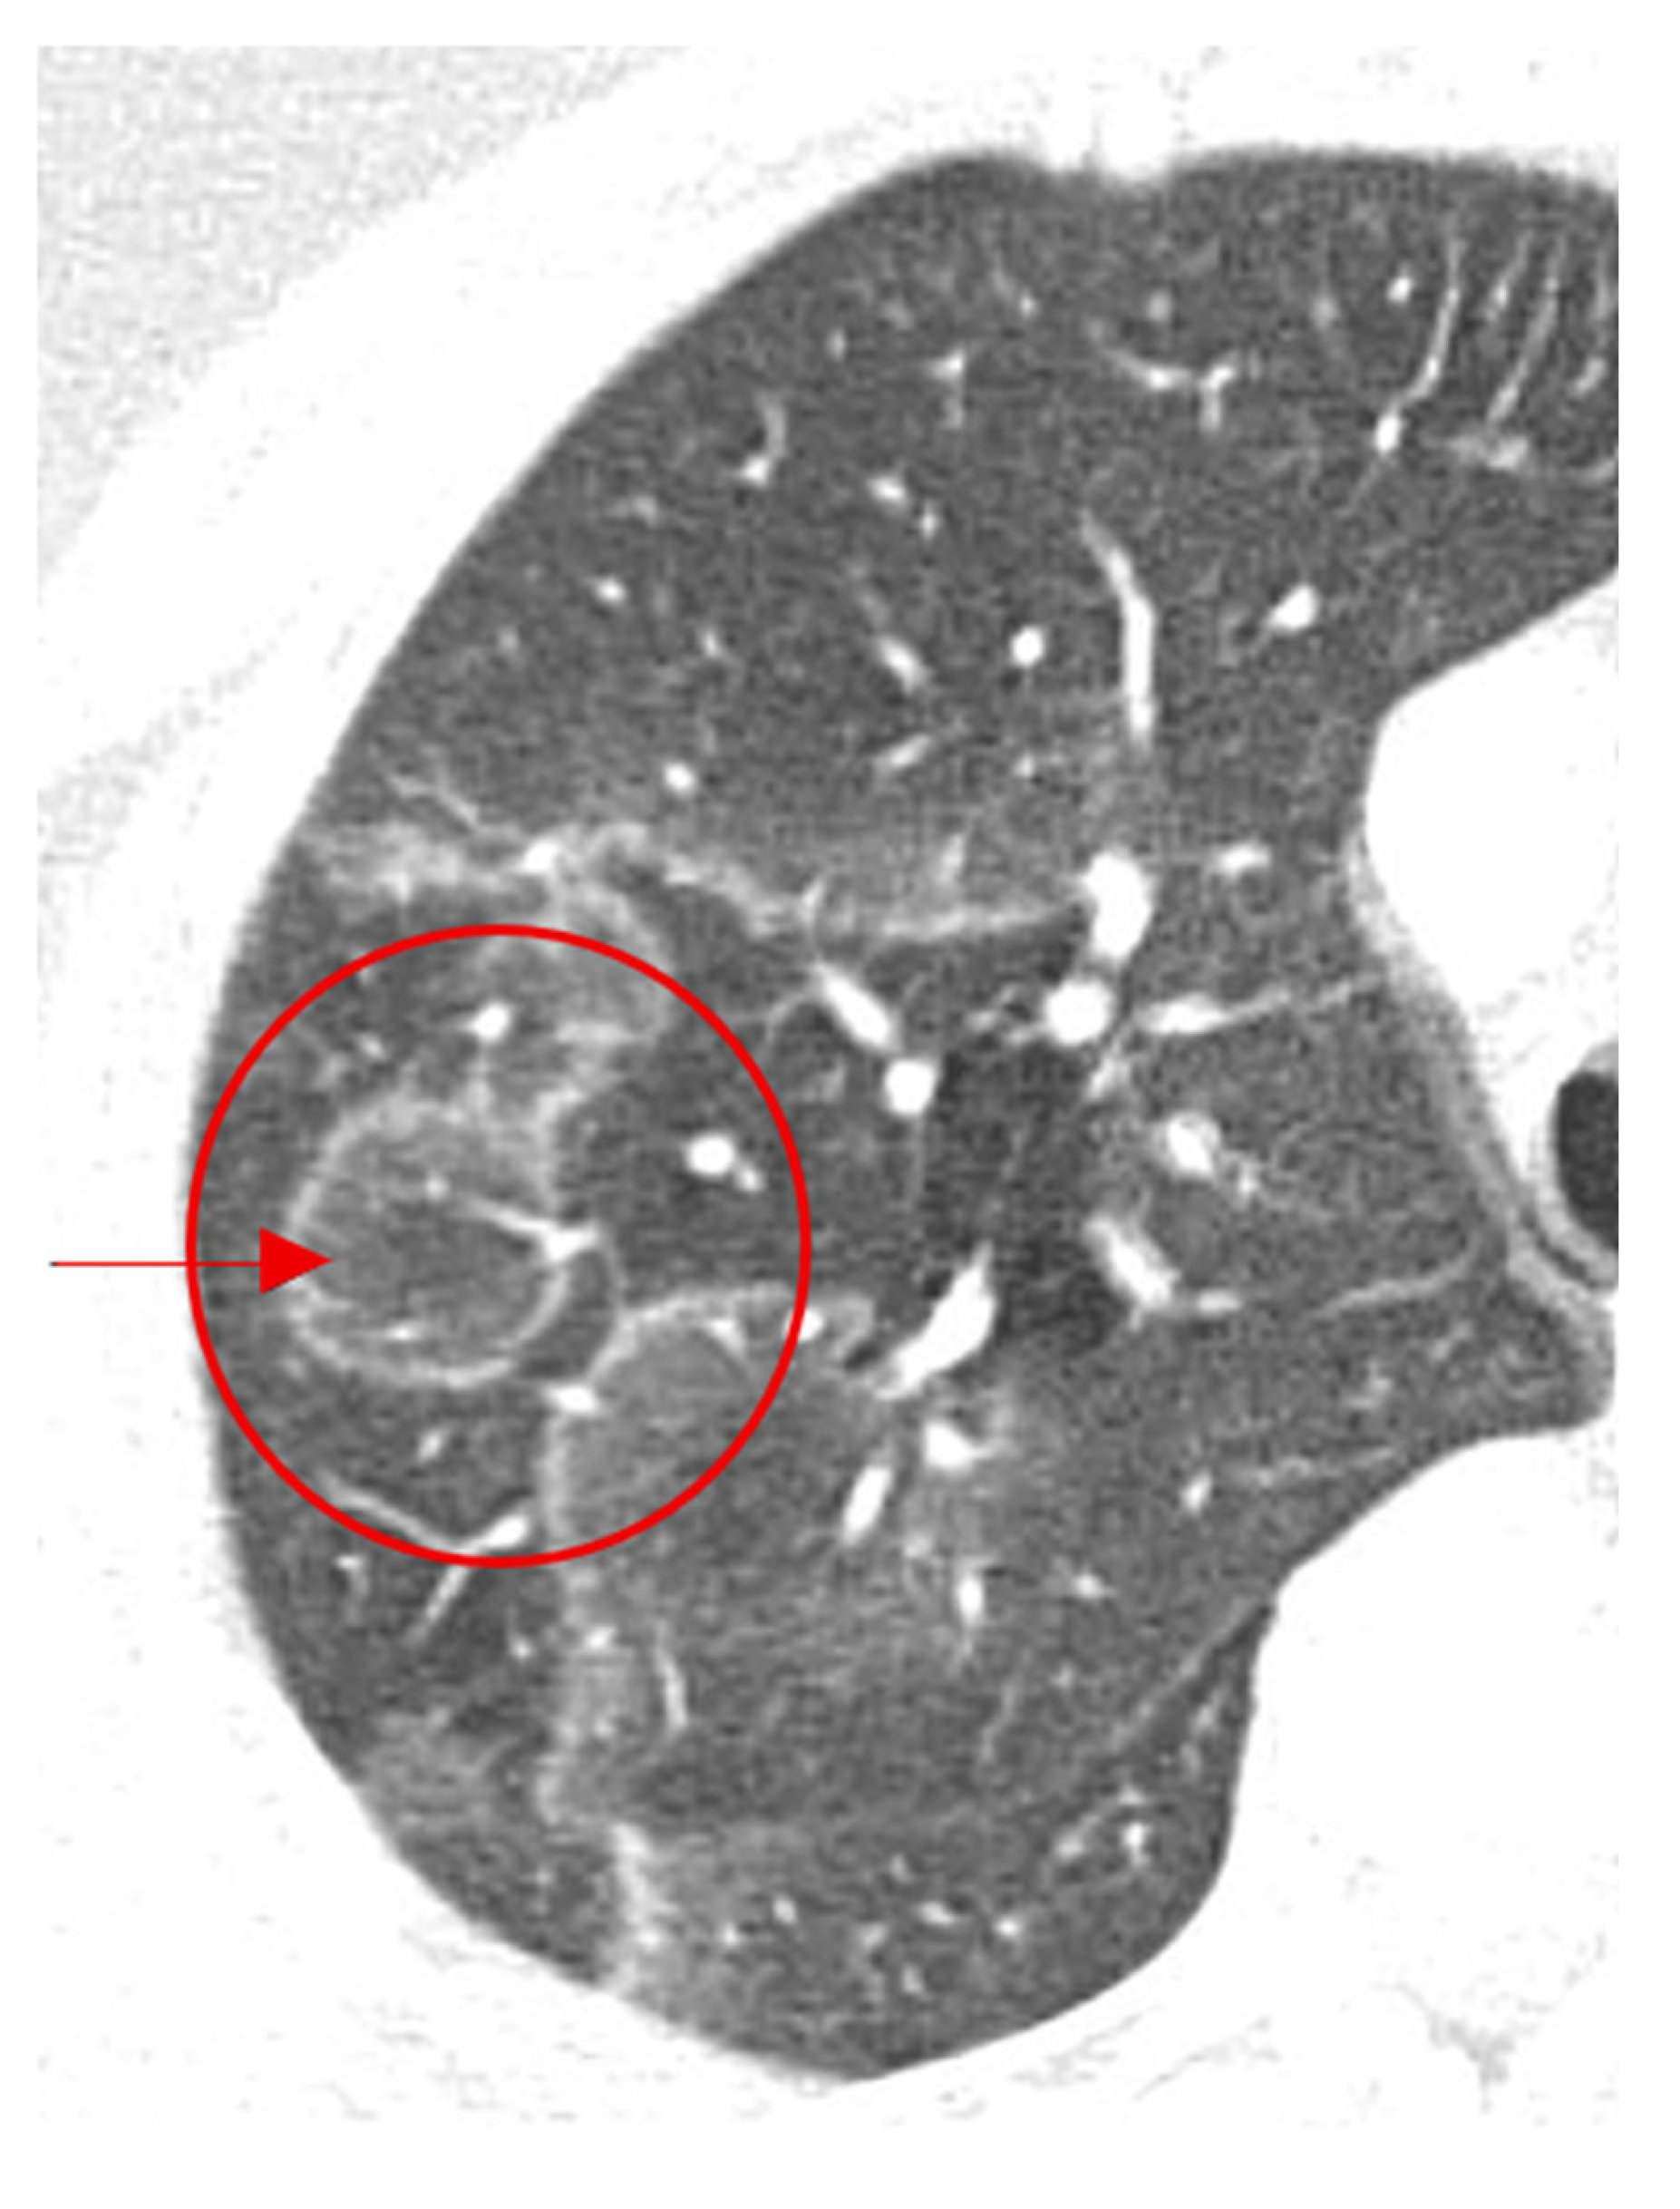

2.15. Halo Sign

- Chiarenza, A.; Esposto Ultimo, L.; Falsaperla, D.; Travali, M.; Foti, P.V.; Torrisi, S.E.; Schisano, M.; Mauro, L.A.; Sambataro, G.; Basile, A. Chest imaging using signs, symbols, and naturalistic images: A practical guide for radiologists and non-radiologists. Insights Imaging 2019, 10, 114. [Google Scholar] [CrossRef]

- Abramson, S. The Air Crescent Sign. Radiology 2001, 218, 230–232. [Google Scholar] [CrossRef] [PubMed]

- Sharma, S.; Dubey, S.K.; Kumar, N.; Sundriyal, D. ‘Monod’ and ‘air crescent’ sign in aspergilloma. BMJ Case Rep. 2013, 2013, bcr2013200936. [Google Scholar] [CrossRef] [PubMed]

- Tseng, Y.Y.; Chen, C.H. Air crescent sign: Not always due to fungal infection. QJM 2015, 108, 255–256. [Google Scholar] [CrossRef] [PubMed][Green Version]

| Air Crescent Sign | CT chest | Invasive pulmonary aspergillosis (IPA), cavitary lung disease | Seen in ~50% of IPA cases; not exclusive | Often coincides with neutrophil recovery in IPA, improving prognosis; must be interpreted with clinical and microbiological data. |